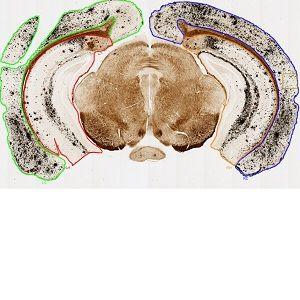

Figure 1

Low magnification overview image showing the 4 regions of interest from a coronal brain section: Left cerebral cortex (green), right cerebral cortex (blue), left hippocampus (red), and right hippocampus (yellow).

The sections analyzed are coronal brain sections. Before applying the image analysis protocol, the Regions of interest (ROIs), the left and right of Cerebral Cortex and Hippocampus, must be outlined manually as shown in FIGURE 1.